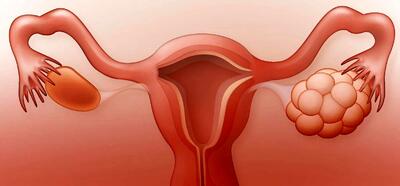

آیا تخمدان پلی کیستیک باعث ناباروری میشود؟

آیا تخمدان پلی کیستیک باعث ناباروری میشود؟ واقعیت این است که سندرم تخمدان پلی کیستیک، اختلالی است که پزشکان آن را با عدم تعادل در هورمونهای جنسی زنانه مرتبط میدانند.